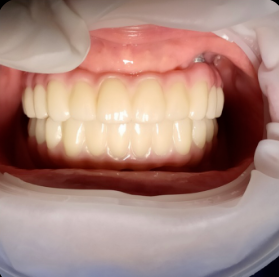

2018년 풀아치 환자분 (당시 40대 남자)

현재도 잘 사용중이세요

잇몸 반응도 지르코니아라 깨끗하구요

곱창집에서 곱창도 드시더라구요..

(곱창집 갔다가 우연히 마주침)